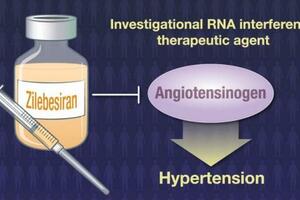

現代營養學認為,柚子皮含有可降低血液粘稠度的柚皮苷,減少血栓形成,有助於預防腦中風。